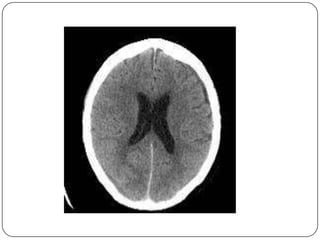

Hemorragia Sub-aracnoidea

   Hiperdensa en la tomografia computada

   Ocupacion de cisuras, surcos y cisternas

   Complicaciones:

hidrocefalia comunicante

vaso-espasmo, isquemia

Hemorragia Sub-aracnoidea  Lesionde vasos perforantes de la pia y aracnoides  Mas frecuente en los extremos de edad  Hiperdensa en la tomografia computada  Ocupacion de cisuras, surcos y cisternas  Complicaciones: hidrocefalia comunicante vaso-espasmo, isquemia

Hueso dura aracnoides Pia cerebro Hemorragia sub-aracnoidea sutil difusa inter-hemisferica intra-ventricular